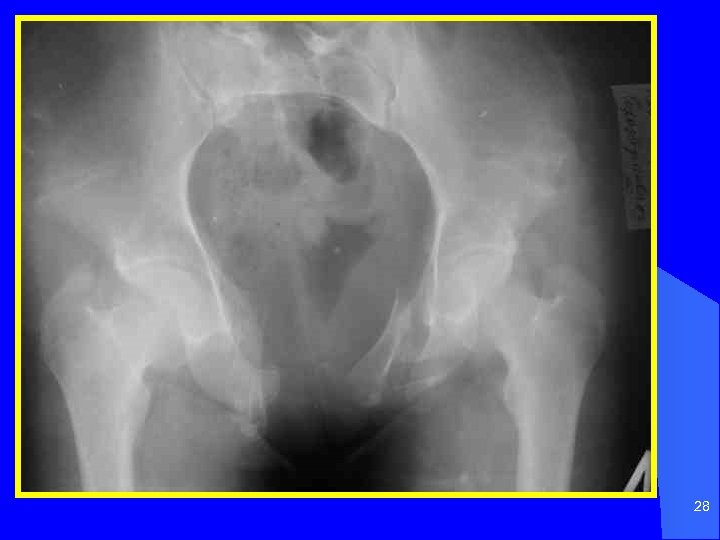

28